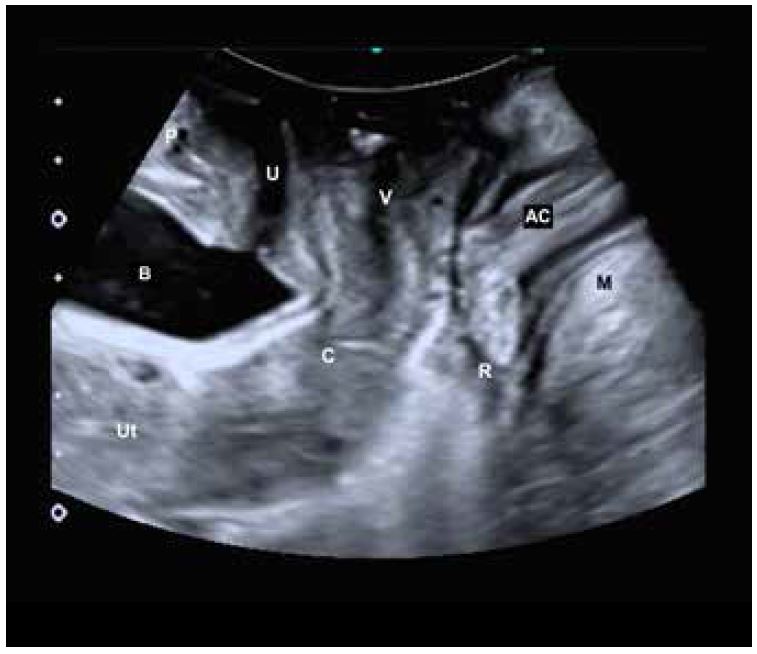

Малюнок 1. Схематичний малюнок датчика та таза. P: Лобок, U: Уретра, B: Сечовий міхур, V: Піхва, C: Шийка матки,    Ut: Матка, AC: Анальний отвір, R: Пряма кишка, M: М'яз-підіймач відхідника (LAM)

Референтною площиною для двовимірного ультразвукового дослідження тазового дна є середньосагітальна площина, ідеальна орієнтація якої виходить із краніо-вентральної області зліва та дорсо-каудальної області справа (мал. 2).

Анатомічні структури, включені в цю площину, зліва направо: лобковий симфіз, уретра та сечовий міхур, піхва та глибше матка, пряма кишка, анальний канал і центр м’яза-підіймача відхідника (LAM) (мал. 2). Під час скорочення LAM наближається до лобка, викликаючи підняття тазових органів, а під час Вальсальви протилежний ефект викликає опускання цих структур.

Малюнок 2. Середньосагітальна площина. P: Лобок, U: Уретра, B: Сечовий міхур, V: Піхва, C: Шийка матки, Ut: Матка, AC: Анальний отвір, R: Пряма кишка, M: М'яз-підіймач відхідника (LAM)